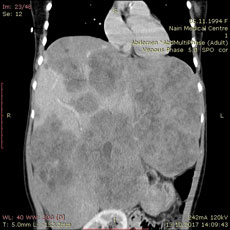

Больной М.М., 1994 г. рожд., поступившей в МЦ Эребуни 03.03.2018г., несколько лет назад было диагностировано очень редкое заболевание: инфантильная гемангиоэндотелиома - быстрорастущее доброкачественное новообразование печени, встречающееся в основном у новорожденных, и, в очень редких случаях, - в более зрелом возрасте, достигая гигантских размеров.

Новообразование размером 25х14х28см занимало всю брюшную полость, верхний этаж таза, сдавливая и смещая внутренние органы. Основным лечением при этой патологии является трансплантация печени или эмболизация артерий узлов для уменьшения их размеров.

03.03.2018г. была выполнена селективная ангиография чревного ствола и печеночных артерий, после чего осуществлена эндоскопическая селективная эмболизация артерий, питающих новообразование, микрочастицами.

В послеоперационный период и последующие недели наблюдалось уменьшение объема и окружности живота и размеров печени. Симптомы сдавления у больной в течение последующих двух недель почти исчезли. Больной рекомендовано динамическое наблюдение и КТ-исследование с контрастированием через 6 месяцев.